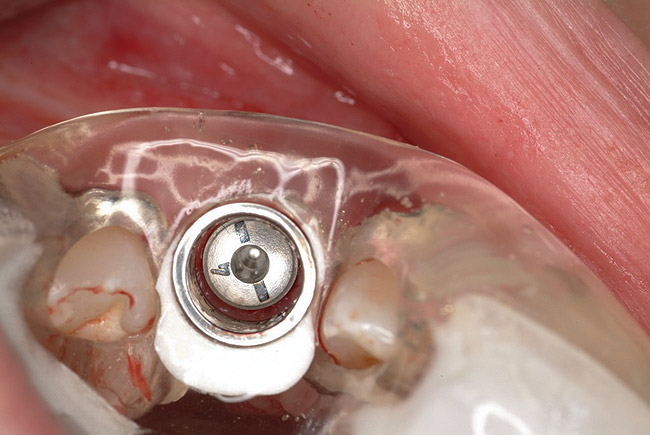

Approximately 4 months after grafting, the patient returned for clinical and 3-D radiographic evaluation. The thinnest area of ridge width preoperatively was remeasured in approximately the same location, demonstrating a gain of about 4 mm (Figure 7). The treatment plan was to place a 3.5-mm x 13-mm implant with a computer-generated guide (SiCat, Sirona Dental, www.sironausa.com), eliminating an additional open surgical procedure. Planning included initial osteotomy preparation with single-use drills combined with a localized ridge expansion using narrow, tapered osteotomes. This was performed approximately 5 months after the augmentation procedure, achieving primary stability of the implant, facilitating a transmucosal healing approach (Figure 8 and Figure 9). Following each step of osteotomy preparation, a probe was inserted along the walls of the site to confirm the integrity of the buccal and palatal walls prior to implant insertion.

Figure 8  Primary stability of the implant achieved, facilitating a transmucosal healing approach.

Figure 8

Figure 9  Primary stability of the implant achieved, facilitating a transmucosal healing approach.

Figure 9